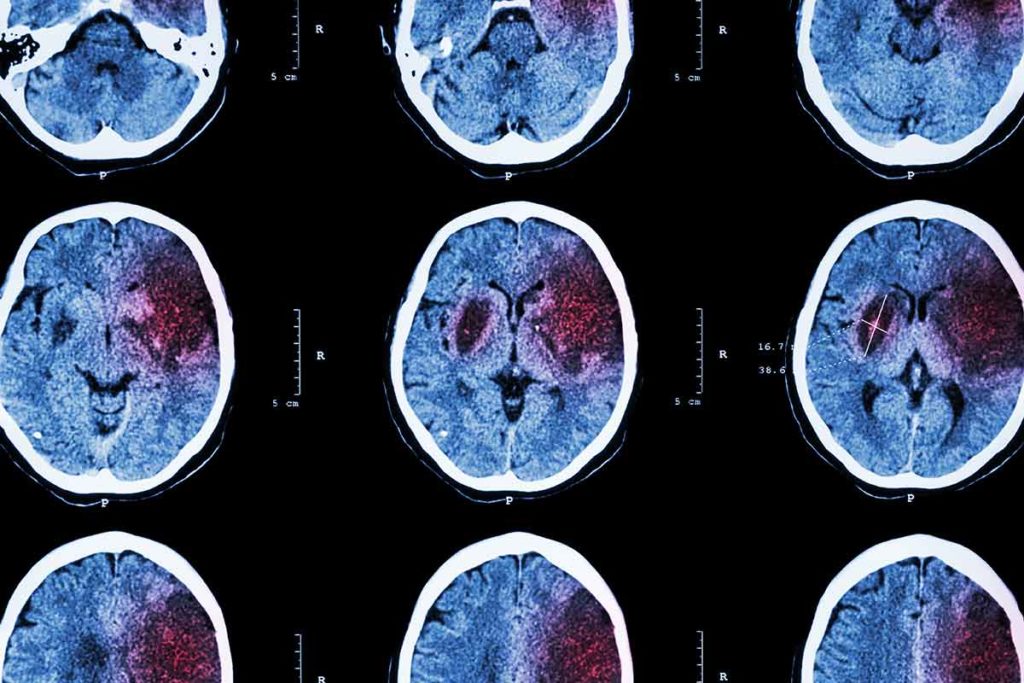

Since the first clot retrieval device received U.S. Food and Drug administration approval in 2004, mechanical thrombectomy has emerged as a standard treatment for large vessel ischemic stroke.¹ While its efficacy is proven, less is known about how to best manage blood pressure in patients following successful mechanical thrombectomy. To find an answer, a team of researchers from118金宝搏抽水宾州国家健康冲程中心和神经外科部门在118金宝搏抽水Penn State Health Milton S. Hershey Medical Center对117例成人急性缺血性卒中患者进行了回顾性研究,接受了机械血栓切除术。结果表明,升高的收缩压(SBP)的个体实例可以显着影响临床结果。

研究人员在机械血栓切除术后的前24小时收集了SBP数据。然后,根据140,160或180mm Hg的SBP病例,它们将患者分为三组。

研究小组使用改良Rankin量表(Rankin Scale)来确定患者90天的功能预后。研究小组还测量了患者在康复的前90天的死亡率、脑水肿和出血率。

结果显示,只有一例收缩压超过180 mm Hg的患者在出院时与不良的功能预后显著相关,而在随访后90天则没有相关性。

考克罗夫特说:“随着时间的推移,我们发现无论病人的血压如何,恢复的水平都开始趋于一致。”“然而,这并不能说明一次收缩压升高的患者是否需要更多的时间进行康复或其他治疗才能达到最佳的康复效果。”该研究还发现,收缩压超过160 mm Hg的一次或多次发生导致恶性脑水肿的几率增加,并有增加有症状的颅内出血几率的趋势。这些发现与中风的严重程度无关。